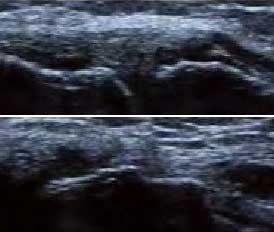

3、准确判断关节积液增加,精准判定RA严重程度

类风湿关节滑膜炎症会导致滑液渗出不断增多,形成关节腔积液。肌骨超声 少可发现1ml的积液,能对关节腔积液量及位置准确定位,通过检测判定关节腔内液性边界清楚的无回声区、细点状回声或细微的低回声条纹,判断其宽度和深度衡量积液量的多少,进而评估RA的严重程度。

在滑膜出现增生前,超声便可定量发现积液

• Ⅰ级微量积液

滑膜囊内见前后径3.55mm液性暗区,呈椭圆形

• Ⅱ级较多量积液

暗区内有团状高回声,可见深度达6.46mm液性暗区

• Ⅲ级大量积液

关节囊扩张,可见大范围液性暗区,髌上囊积液深度达11.2mm